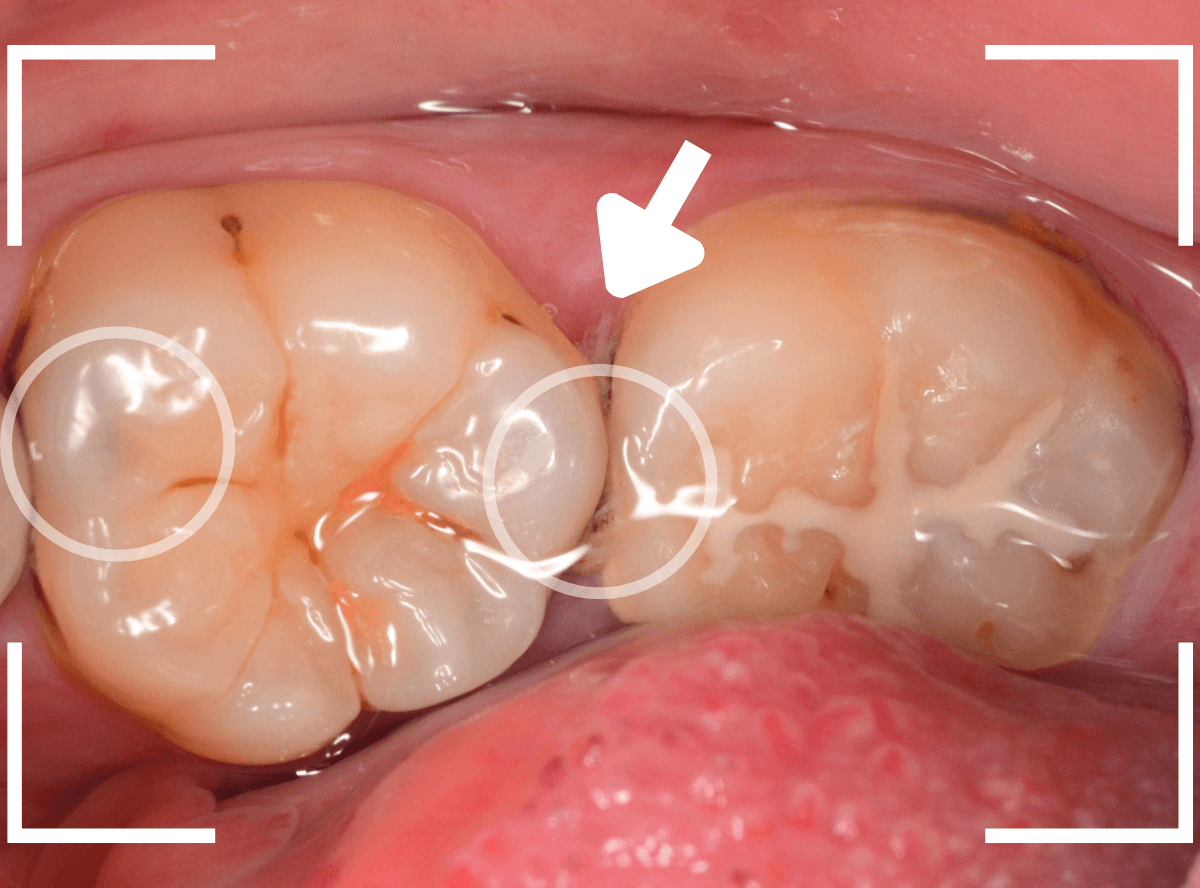

Case.13 歯と歯の間の虫歯が4本続いたケース

他の歯の虫歯の治療で来院された方で、下の歯の奥歯に虫歯が見つかった方です。

レントゲン写真で、歯と歯の間が虫歯になっているのがわかります。

手前の歯の状況です。

〇部のやっと黒く見えている部分が虫歯です。

後ろの歯の状況です。

〇部に虫歯がある他に、矢印部、歯と歯の間に物がつまっているのが見えます。

このような状況の時は、中で大きな虫歯になっている事が多いです。